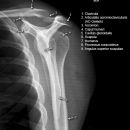

Schulter seitlich (Y-View)

Bei Luxation zusätzlich zur glenoidtangentialen Aufnahme problemlos durchführbar! Axiale Aufnahme schmerzbedingt meist nicht möglich.

Beurteilungskriterien

- Skapula bildet sich als Y ab

- Humeruskopf projiziert sich in das Glenoid? Luxation? Luxationsrichtung?

- Weite des subacromialen Raumes exakt nur in der 10 – 15° nach kaudal angulierten Aufnahme bestimmbar („Morrison, Outlet View“)! Normalerweise 1 - 1,5 cm, < 6 mm -> wohl pathologisch, Impingment wahrscheinlich

- Normvarianten: Os glenoidale (akzessorischer Ossikel kaudal des Glenoids), persistierende Akromion- oder Korakoidapophyse, entwicklungsbedingte Pfannenranddefekte

- Schulterluxationen:

- Anteriore Luxation (2) 95%= anteriore infraglenoidale Luxation, Kopf liegt vor Glenoid

- Posteriore Luxation (2) 3%: wird häufig übersehen! Kopf liegt hinter Glenoid, Hochstand des Humeruskopfes, fixierte Innenrotation des Humeruskopfes => atypische Projektion des Humeruskopfes: “ drumstick or bulb appearance“ (Birnenform), Muldenzeichen („trough line“), „rim sign“ in der ap bzw. glenoidtagentialen Aufnahme.

Zweite Ebene, z.B. transskapuläre Aufnahme zeigt die Richtung der Luxation. Cave. rein klinische Diagnose!

- Begleitverletzungen? (-> heute umfassend mit CT/MRT zu beurteilen)

- Tuberculum majus (15%)

- Pfannenrand

- Hill- Sachs Läsion = Dorsokraniale Humeruskopf-Impressionsfraktur (50%) (Aufnahme der 1. Wahl: Stryker oder CT)

- umgekehrte Hill-Sachs Läsion = anteromediale Impression nach hinterer Luxation

- Bankart-Läsion: Abriss des vorderen Labrum-Kapsel-Komplexes bzw. Abrissfraktur des vorderen unteren Glenoidrandes (-> CT-Athrographie, Arthro-MRT)